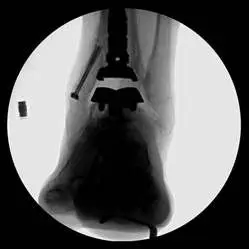

These are pics of the fusion prior to takedown

These first three pics are placement of screws in the medial malleolus and distal fibula to aid in stability.